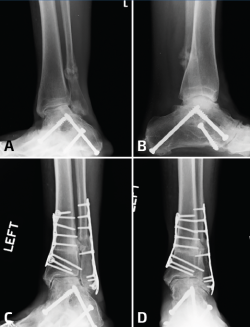

La selección de la osteotomía y el tipo de injerto para la reconstrucción va a depender de la posición de la mala consolidación; recuerden que el peroné puede estar acortado o rotado a externo, o bien acortado y rotado a interno. Idealmente, no sería necesario desprender la sindesmosis en su totalidad para elongar el peroné (Figura 3). Si el peroné está rotado hacia afuera y no está acortado, entonces se puede realizar una osteotomía rotacional sin elongación y, de esta manera, se preserva la sindesmosis, aunque esto no es una condición frecuente. El objetivo del tratamiento de la consolidación viciosa del peroné consiste en restaurar la correcta longitud y la rotación, para obtener una alineación anatómica del astrágalo dentro de la mortaja del tobillo. Sin embargo, también es importante reconocer otros aspectos del patrón original de la fractura.

Figura 3. En este paciente, además de la pseudoartrosis del peroné, se asocia un gran defecto osteocondral del astrágalo (A, B, C). Para acceder a la lesión, se realizó una osteotomía en la región lateral de la tibia (D, E, F). Después de la colocación de los injertos tomados de la rodilla, se realizó la osteosíntesis de la osteotomía de la tibia y posteriormente se trató la pseudoartrosis del peroné (G, H).